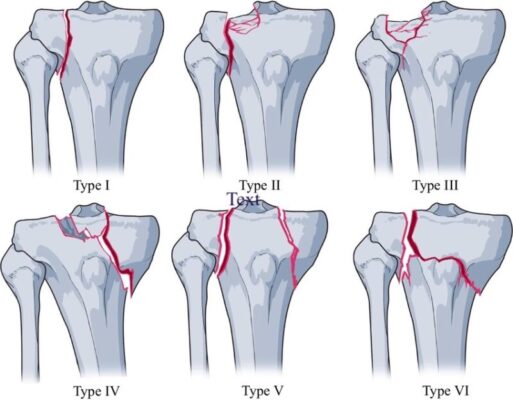

a) Phân loại Schatzker (1979):

Phân loại Schatzker dựa trên hình thái gãy xương trên X-quang, chia gãy mâm chày thành 6 loại chính, từ đơn giản đến phức tạp, dựa trên vị trí và đường gãy:

- Loại I: Gãy chẻ dọc mâm chày ngoài (Wedge fracture of the lateral tibial plateau). Gãy đơn giản, đường gãy dọc, thường do lực ép vẹo ngoài (valgus force) ở người trẻ xương còn chắc khỏe.

- Loại II: Gãy chẻ dọc mâm chày ngoài kèm lún (Split-depression fracture of the lateral tibial plateau), đường gãy dọc kết hợp với lún mâm chày ngoài. Thường gặp ở người lớn tuổi có xương yếu hơn.

- Loại III: Gãy lún đơn thuần mâm chày ngoài (Depression fracture of the lateral tibial plateau). Lún thuần túy mâm chày ngoài, không có đường gãy chẻ dọc rõ ràng. Gặp ở người loãng xương.

- Loại IV: Gãy mâm chày trong (Medial tibial plateau fracture). Gãy mâm chày trong, có thể chẻ dọc hoặc lún. Thường do lực ép vẹo trong (varus force) hoặc lực nén mạnh. Tiên lượng xấu hơn loại gãy mâm chày ngoài.

- Loại V: Gãy hai mâm chày (Bicondylar fracture). Gãy cả mâm chày ngoài và trong. Gãy phức tạp, thường do lực tác động mạnh.

- Loại VI: Gãy mâm chày kèm di lệch thân xương chày (Tibial plateau fracture with metaphyseal-diaphyseal dissociation). Gãy phức tạp nhất, bao gồm gãy mâm chày và phần trên thân xương chày. Thường do lực tác động năng lượng cao.